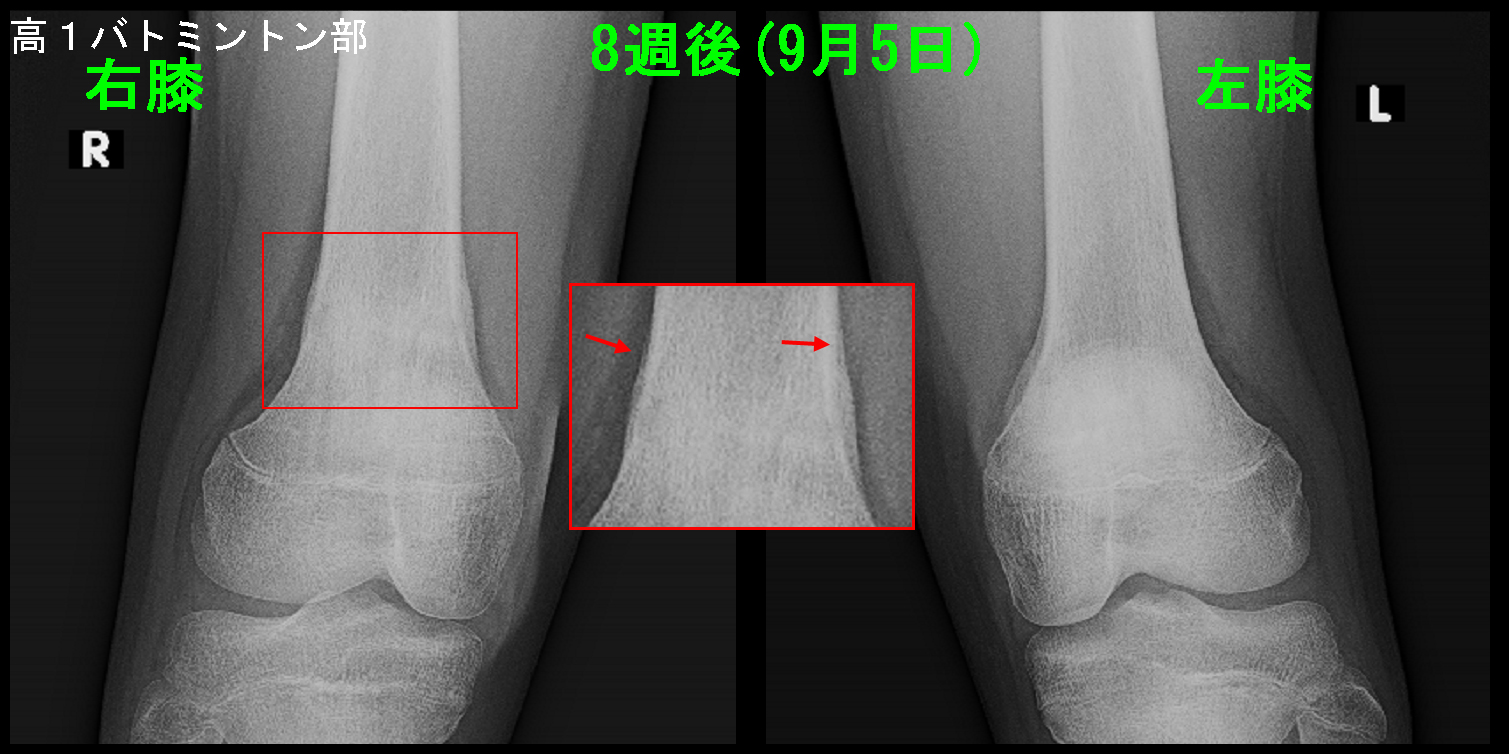

当院受診から、8週後レントゲン像で仮骨は成熟し、練習を開始しています。

8週後Xp.jpg